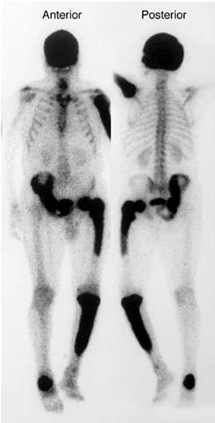

paget disease of bone

A 72-year-old man presents for a routine follow-up in his general practitioner's office regarding his type 2 diabetes and hypertension management. He reports feeling generally well, with no specific complaints of bone pain, fractures, or changes in his hat size. His past medical history includes well-controlled type 2 diabetes mellitus, essential hypertension, and obesity. He denies any recent falls or trauma.During the visit, his vital signs are stable: temperature 36.80C, blood pressure 130/80 mmHg, pulse 70/min, respirations 16/min, and oxygen saturation 98% on room air. Physical examination is unremarkable, with no bony tenderness or deformities noted. Routine laboratory tests ordered during his visit reveal several abnormal findings.Given the patient's presentation and laboratory findings, what is the most likely diagnosis and the initial management strategy?